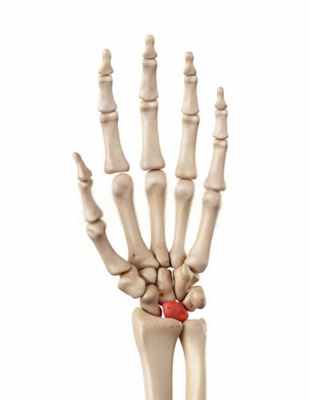

Болезнь Кинбека (Kienböck disease) — это проблема в запястье, связанная с нарушением кровоснабжения полулунной кости. Полулунная — это одна из тех восьми маленьких косточек, которые составляют запястье. В запястье выделяют два ряда: тот, что ближе к предплечью называют проксимальным, другой, который ближе к пальцам — дистальным. Полулунная кость находится в самом центре проксимального ряда, она неразрывно связана с ладьевидной костью, которая соединяет оба ряда запястья. Согласно биомеханическим исследованиям порядка 70% нагрузки на лучезапястный сустав ложатся именно на полулунную кость.

Болезнь Кинбека (m. Kienbock) - остеонекроз полулунной кости. Заболевание имеет и другие синонимы (остеохондропатия полулунной кости, деформирующий остеохондрит запястья, травматический остеопороз костей запястья, лунатомаляция, асептический некроз полулунной кости запястья, аваскулярный некроз полулунной кости), но в настоящее время принято считать корректным именно трактовку "остеонекроз" полулунной кости. Впервые описано австрийским врачом рентгенологом R. Kienbock в 1910 году.

Полулунная кость - одна из восьми костей запястья.

Кости запястья.